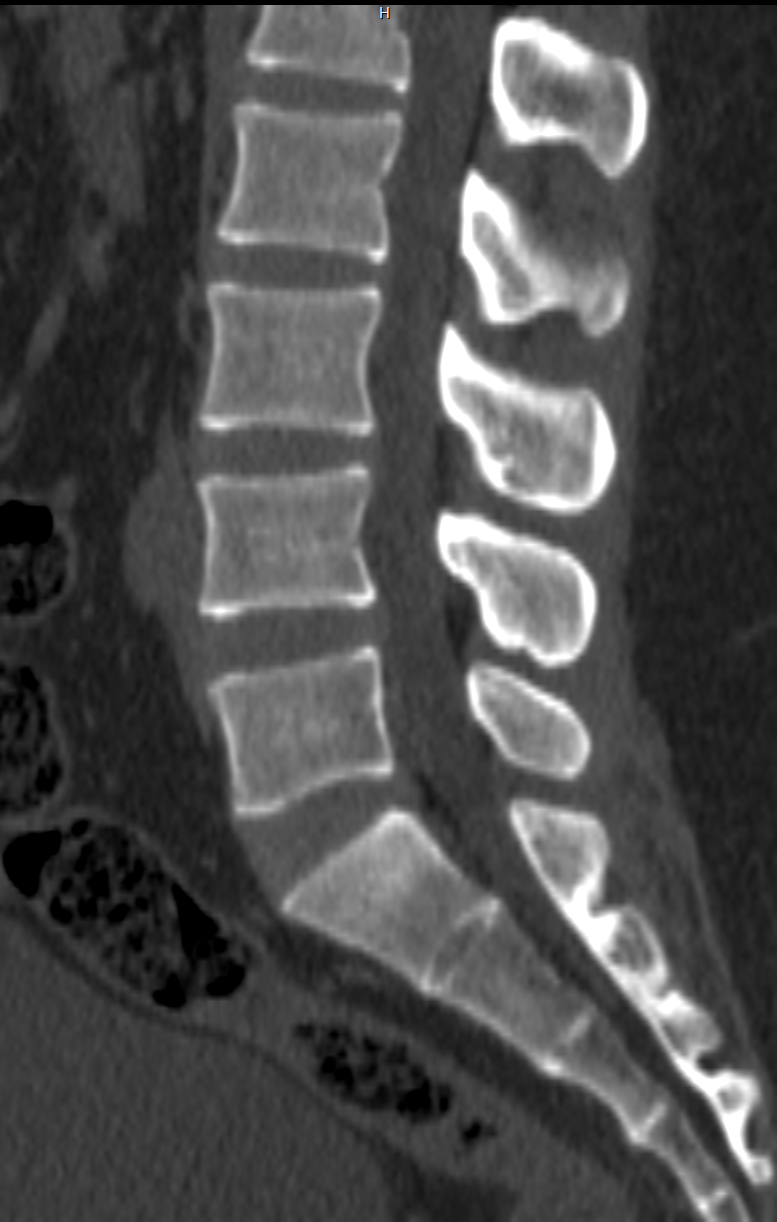

One of the most common uses of a CT scan machine is evaluating trauma and injuries, particularly those affecting bones, joints, and soft tissues.

A CT scan machine can reveal:

Fractures

A CT scan machine is essential for quickly assessing fractures — such as broken ribs, skull fractures, or spinal injuries — from traumas like car accidents or falls. It provides detailed images that can reveal breaks invisible on traditional X-rays, which help doctors see if bones are displaced or if nearby tissues (like muscles or nerves) are damaged.

Joint Disorders

A CT scan provides detailed images that are crucial for diagnosing joint-related conditions such as arthritis, degenerative changes, and bone spurs — all potential sources of pain and restricted mobility. By clearly revealing the extent of damage within the joint, it enables clinicians to accurately assess severity and make informed decisions regarding treatment, whether that involves physical therapy, medication, or surgical intervention.